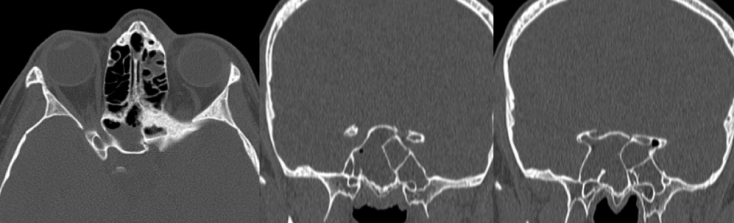

fracture du canal optique gauche avec rhinorrhée droite du fait de l’asymétrie de la cloison du sinus sphénoïdal - étage postérieur : correspondant à la face postérieure du rocher, il est en rapport avec l’oreille moyenne et les cellules mastoïdiennes, ces dernières ont la particularité de ne pas avoir de muqueuse.